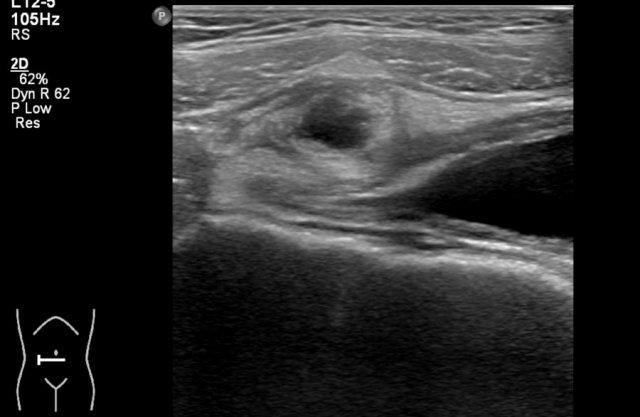

Hình ảnh siêu âm cho thấy một tổn thương dạng nang ở vùng bụng dưới của một bé gái 3 tuổi với đau bụng từng cơn.

Trong phẫu thuật, phát hiện xoắn phần phụ phải.

Giải phẫu bệnh xác nhận là u quái (teratoma).